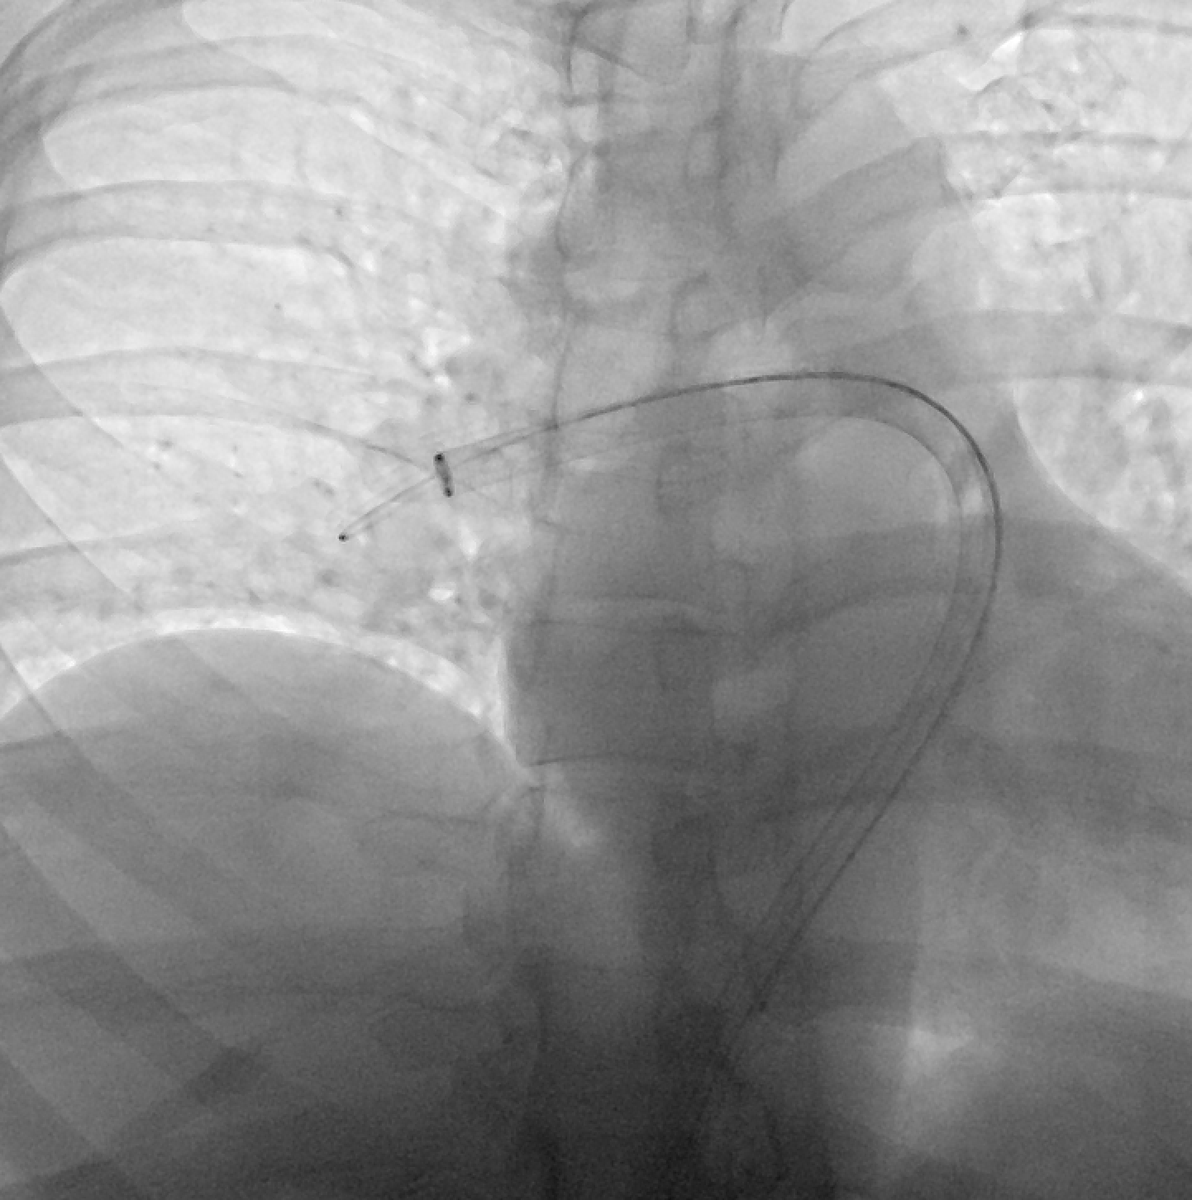

From there I advance the angled pigtail into the main PA and measure pressure. In this case was 64/33 mmHg. I do a PA-gram but its a hand injection and only to confirm where I am before measuring. I use CTA info and try to approach the thrombectomy similarly for all cases (5/ )

Next, I take the angled pig into the RLL PA (Cordis 6Fr 110cm). I take another hand injection to confirm location of my catheter. I then *important* remove the catheter over the 1cm floppy, exchange-length amplatz taking care to maintain the distal wire knuckle (6/ )

The wire knuckle is key, as it allows you to place a little forward tension on your thrombectomy catheter as you advance it from main PA to the RLL PA. Now, I remove the 6Fr sheath, place the 24 Fr Dryseal and advance my T24 flex into the RLL pulmonary artery. (7/ )